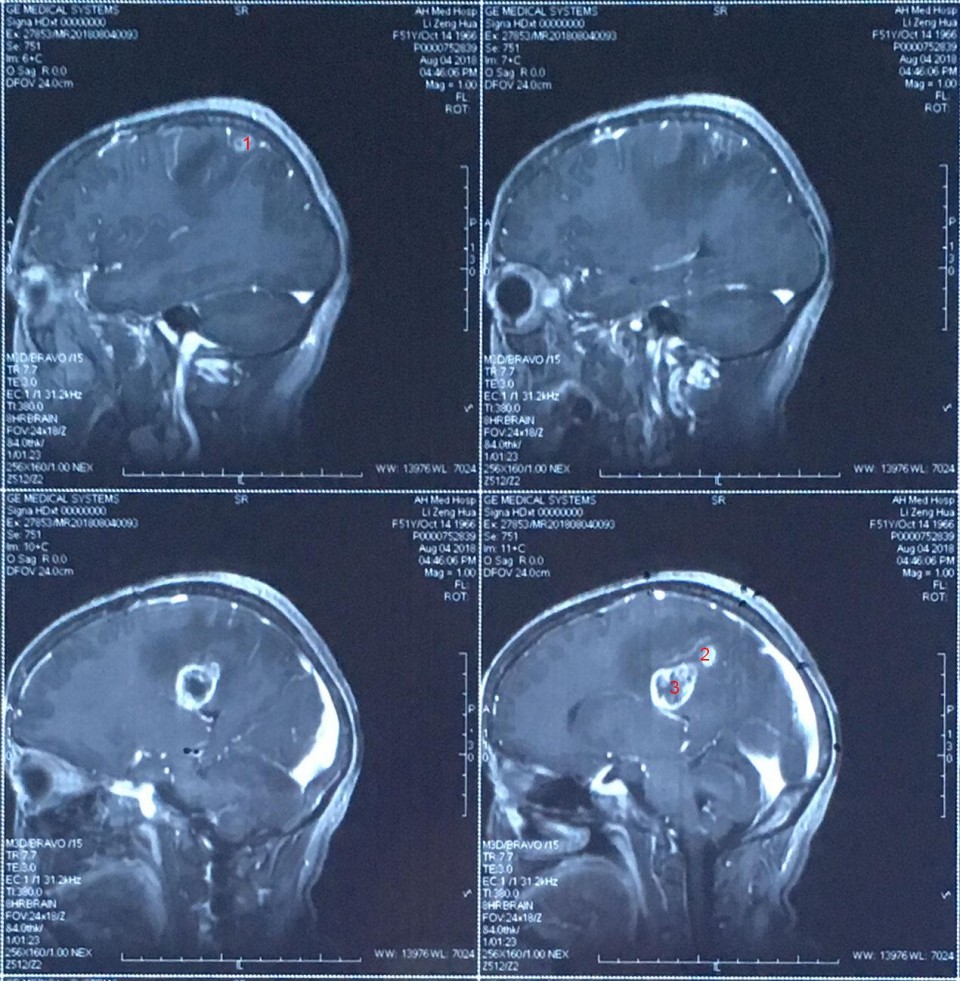

术前患者MRI提示颅内多发肿瘤

患者,女,51岁,系头痛头晕1月余”入院,入院后完善相关检查,专科检查:神清,精神差,双瞳孔等大等圆,光敏(+),左侧肢体肌力IV级别,右侧肢体肌力正常,余检未见明显异常。头颅MRI检查示:颅内多发性肿瘤,考虑转移瘤可能。遂行PET-CT检查未发现颅外原发性病灶。完善术前常规相关检查,未见明显手术禁忌后,于全麻下圆满完成术中B超引导下一次性切除颅内多发肿瘤手术,在经过家属及护理部的精心护理,患者术后恢复良好。